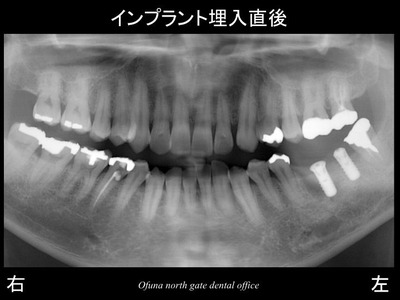

以下がインプラントを埋入した直後です。